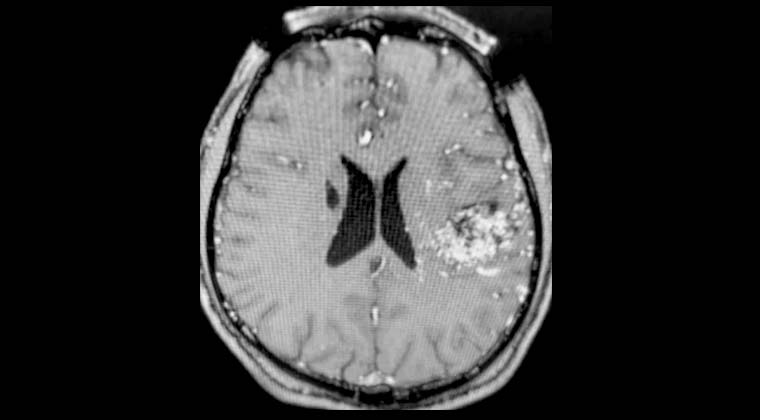

② Случай 2:

Пациентка: женщина, 56 лет

Жалобы: слабость в левой стороне тела, нарушение походки в течение 2 недель. Диагноз: множественные метастазы рака легких в головной мозг.

Рисунок 1: 25.02.2022 Планирование лечения Гамма-ножом опухоли в правой лобной доле, выраженный перифокальный отёк.

Рисунок 2: 25.02.2022 Одновременно проведено лечение Гамма-ножом опухоли в левой височной доле.